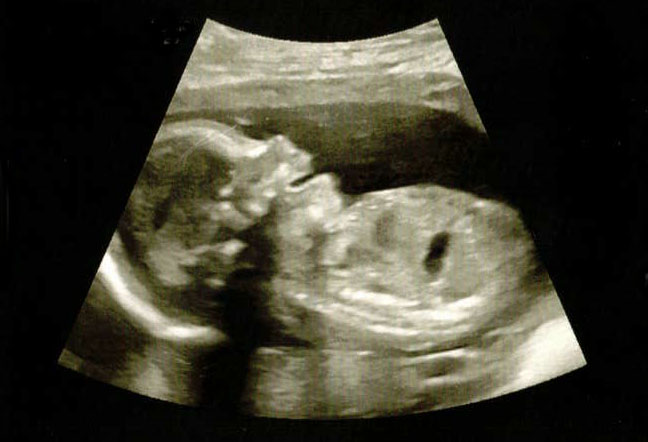

Birth is a powerful experience that requires a woman to feel safe, supported and as calm as possible to move through the waves and bring their baby Earthside. Who you have supporting you is an important decision and I am honoured that you are considering working with me. I believe in being fully informed by your care provider about all options available to you at every step of the way through pregnancy, birth and beyond. Knowledge is power and there is no greater time to learn about advocating for your child than while they are still in utero. I’ll be beside you, supporting you with seeking information, being an ever-growing resource to you and cheering you on into postpartum and beyond!